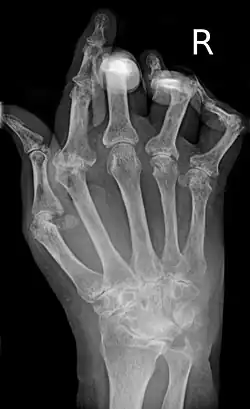

U kloubu dochází k poškození ve dvou úrovních. Nejprve u časné formy RA dojde vlivem zánětu ke ztluštění synoviální membrány a vylučování tekutiny do kloubu. Synovitida neboli zánět synoviální membrány se typicky projevuje bolestí, otokem a ztuhlostí kloubů a vede ke snížené pohyblivosti. Pokud není léčena, vede k destrukci kloubu, která je patrná na rentgenových snímcích jako erozivní poškození v místech úponu synoviální membrány ke kosti a případné zúžení kloubní štěrbiny[25]

- Rentgenové vyšetření – rentgenové snímky se pořizují pravidelně v průběhu nemoci. Pro lékaře je důležitá možnost srovnat rentgenové snímky z různých časových období a určit tak, zda a jak rychle postupuje zánětlivý proces poškozující klouby.